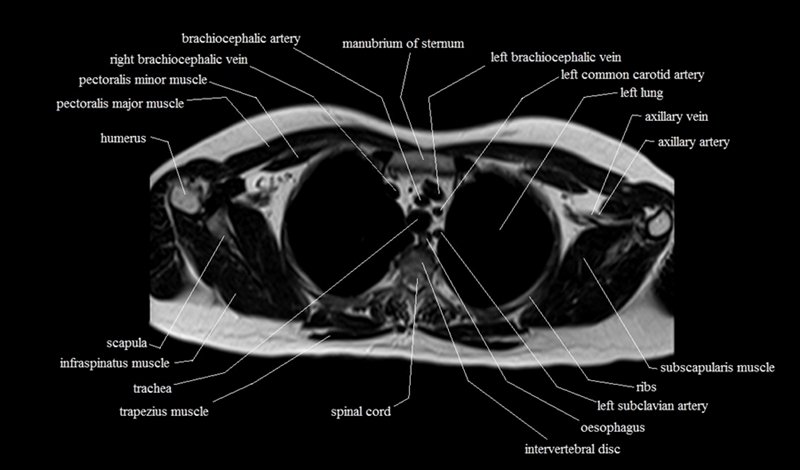

MRI Axial Cross Sectional Anatomy of Chest

This MRI chest (thorax) axial cross sectional anatomy tool is absolutely free to use. Use the mouse scroll wheel to move the images up and down, or alternatively, use the tiny arrows (→) on both sides of the image to navigate through the images. For a more detailed view, double-click the image to view it in full screen, and use the menu in the top right-hand corner to view individual slides or play them in a loop.